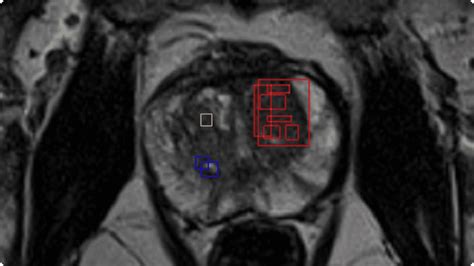

• Artificial intelligence (AI): AI algorithms are being developed to assist radiologists in interpreting prostate MRI images. These algorithms can help to identify subtle changes in the prostate that may indicate cancer, improving diagnostic accuracy.

• Fusion imaging: Fusion imaging combines MRI images with ultrasound images to provide a more accurate and detailed view of the prostate. This can be particularly useful for guiding prostate biopsies and planning treatment.